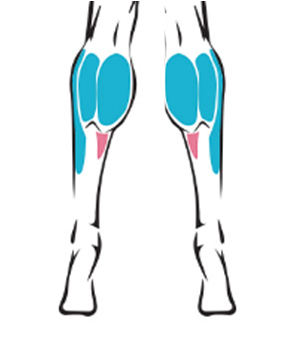

ハピス超音波ふくらはぎ形成術の特徴

一度の精密施術で、構造を可視化しながら矯正します。

ハピスの超音波ふくらはぎ形成術は、高解像度医療用超音波機器を用いて、施術前・中・後の全過程をリアルタイムで確認します

神経の位置

神経の深さ

筋肉の厚さ

血管分布

筋膜構造

従来法が解剖学的平均位置や電気刺激反応に依存していたのに対し、

ハピスは個々の実際の構造を直接確認しながら行う画像誘導施術(Ultrasound-guided procedure)です。